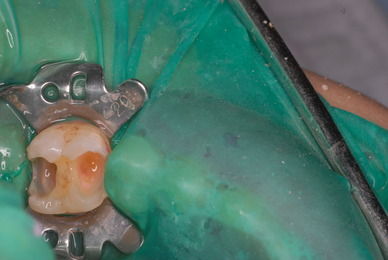

今では染色液がありますから取り残しなど少ないと思われますが、実際に取れたという銀歯を持ってきた患者さんの歯を見ますと、虫歯の取り残しを痛感いたします。

もし取れなくても中で拡がると神経を損傷し、しみるとか最悪の場合神経を取らなくてはならなくなります。

写真は典型的な取り残したまま銀歯を入れていた方のものです。よくぞ痛くならなかったものです。

意外と手間取り一時間以上かかりセメントを入れてとりあえず終了いたしました。神経が近いので傷つけて損傷すると助かる見込みが少なくなり、痛みが出て死んでしまうとか膿んでしまうこともあるのです。![570b1c06-s[1]](https://livedoor.blogimg.jp/netdental/imgs/6/0/60221eb2.jpg)